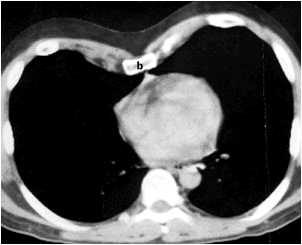

the body of the sternum is displaced posteriorly

and rotated.